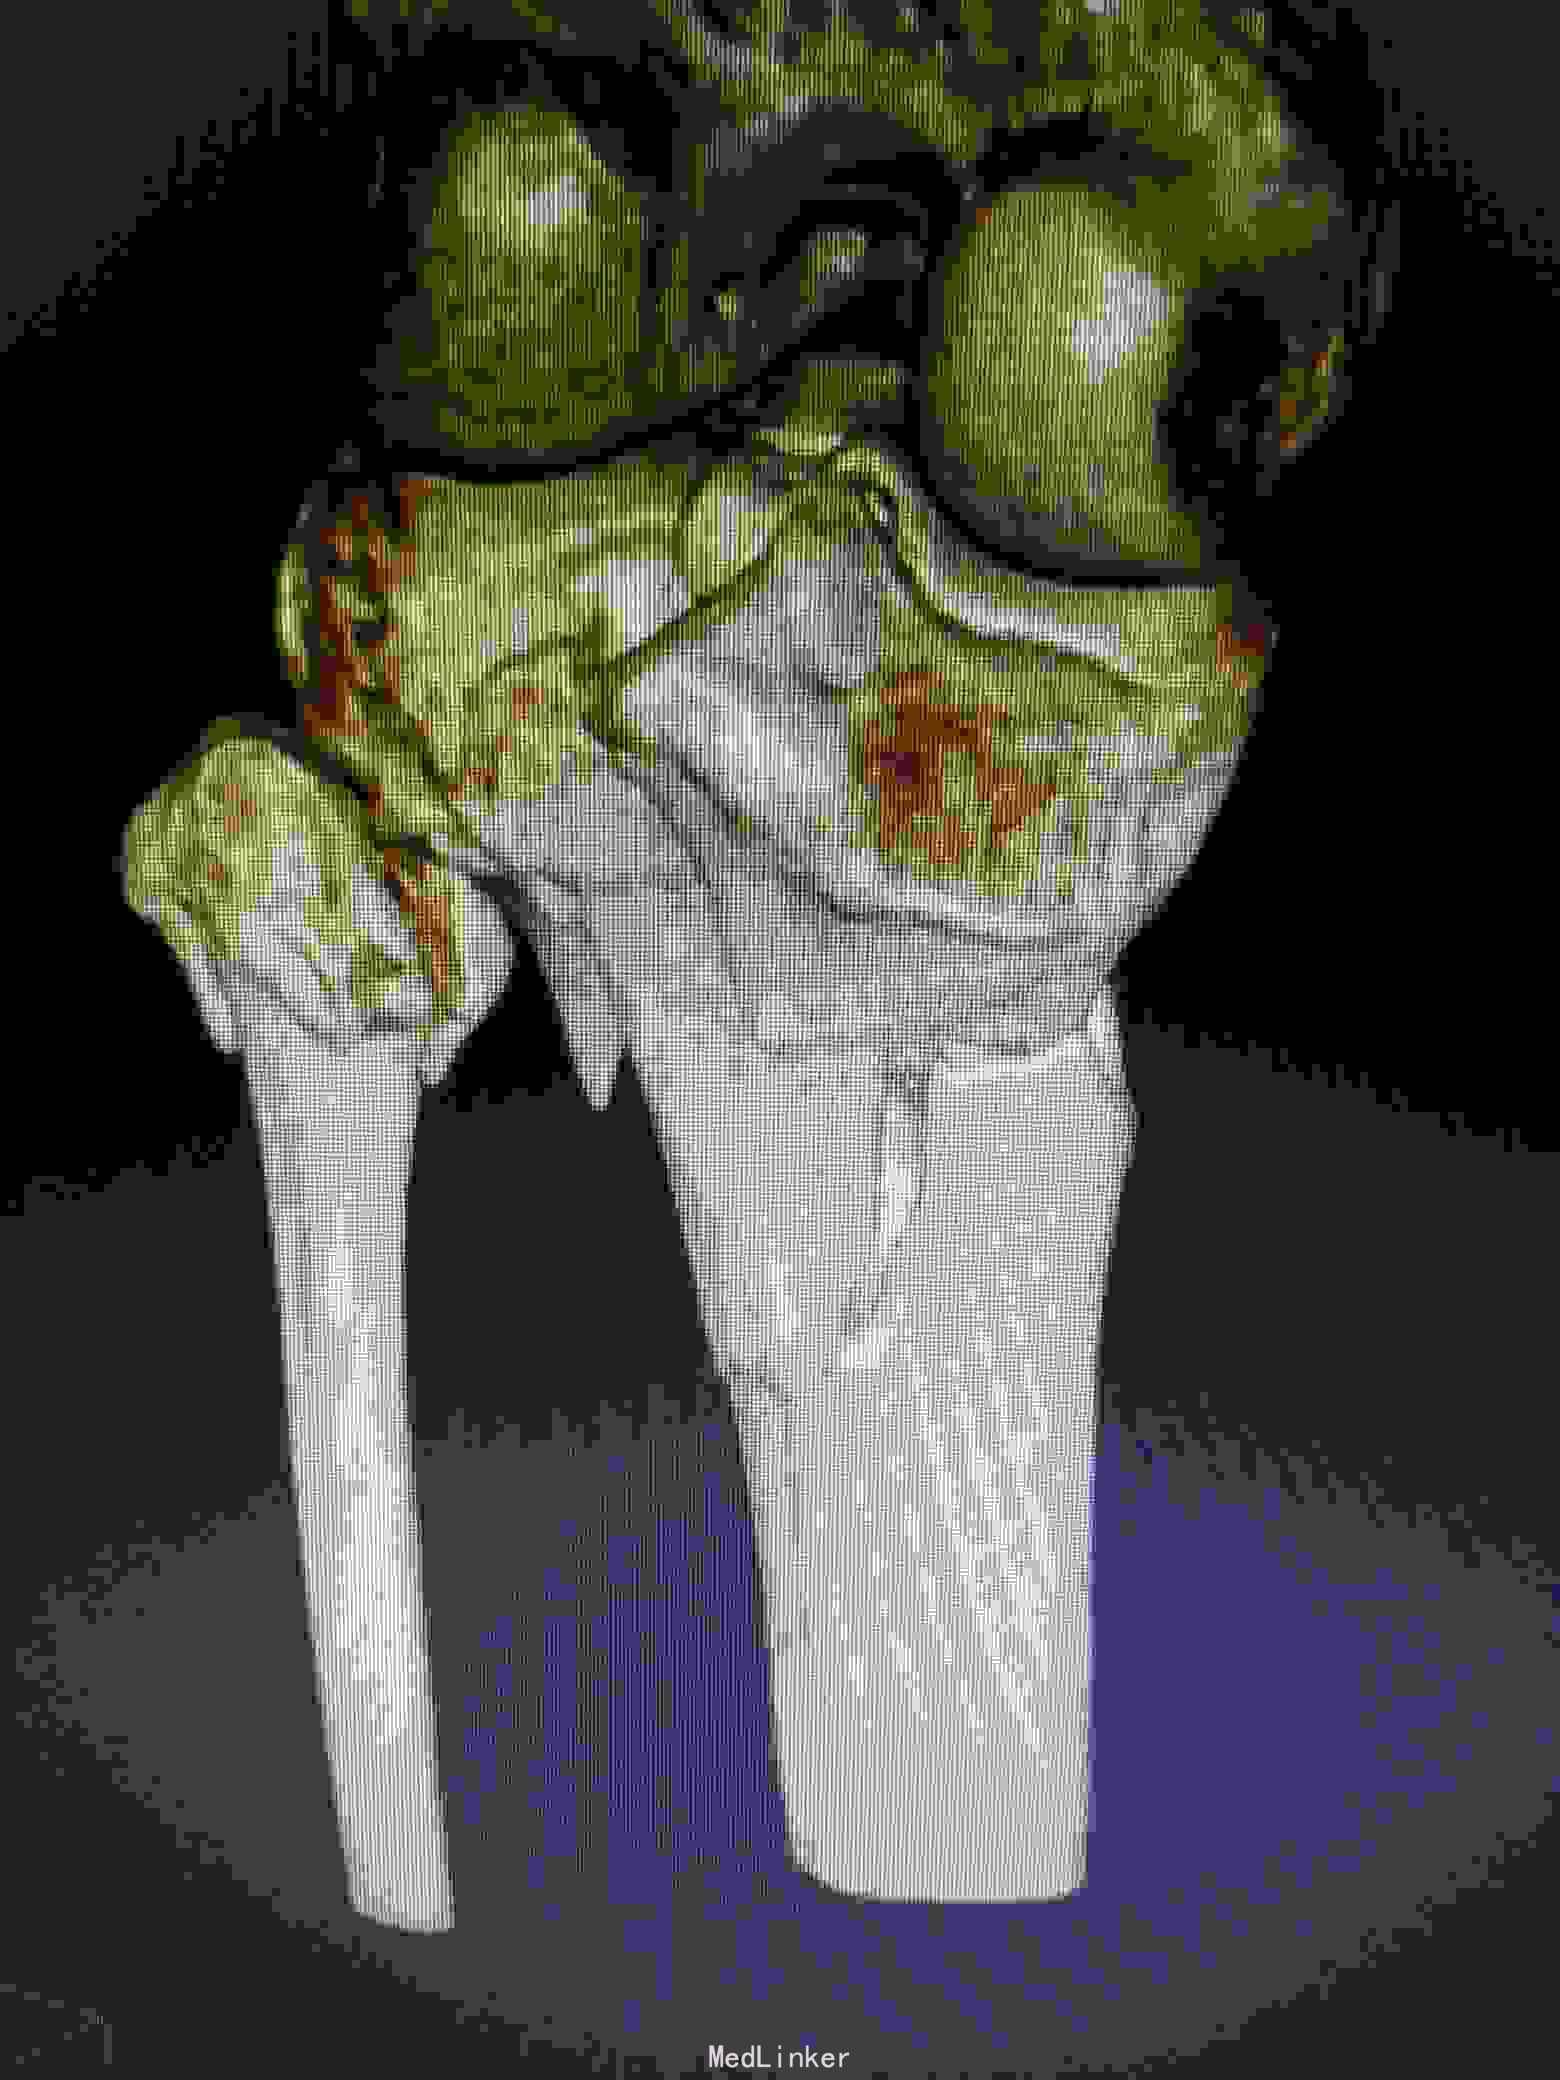

患者,男,35岁,摔伤致左膝肿痛,活动受限4小时入院。

入院查体:局部肿胀明显,无神经血管损伤体征,入院给予跟骨牵引等对症治疗。完善影像学检查。

诊断:左胫骨平台粉碎性骨折(5型)。

治疗:采用俯漂体位,先行俯卧,行后内侧入路,显露胫骨平台后内侧,可以清楚显露后内侧及内侧,可以同时固定后内侧及内侧骨块。然后再漂致仰卧位,行前外切口行前外侧的钢板固定。